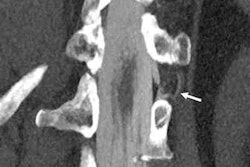

In a related presentation, Margarida Ribeiro, PhD, of Universidade Nova de Lisboa in Portugal explored chest CT protocols during the pandemic and their influence on patient radiation exposure. She and colleagues examined chest CT protocols used in five hospitals for 25 patients, tracking parameters that impact the exam's CT dose index volume (CTDIvol) and dose length product, or DLP (thickness, pitch, kV, mA, time rotation, and gap).

Ribeiro's group found no statistically significant differences among the five COVID-19 chest CT protocols in the evaluation of effective dose measured in mSv, although there was a range of doses across the five hospitals (2.94 mSv to 6.68 mSv). She reported that the lowest dose chest CT protocol resulted in an 89% reduction in radiation exposure without negative affect on diagnostic accuracy.